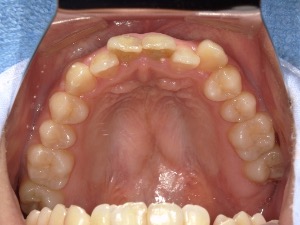

before

患者さんの年齢 20代 女性 症状 ガタガタを治したい 治療内容 マウスピース矯正治療 費用 90万(税抜) 治療期間・回数 治療期間2年、通院回数10回 メリット 笑顔が綺麗 デメリット・リスク 期間がかかることがある - マウスピース矯正